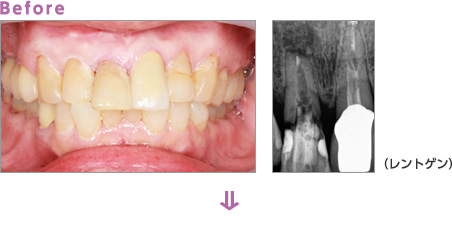

歯周病治療

さまざまな要因を改善することが歯周病治療の始まりです。

まずはカウンセリングやブラッシング指導で生活習慣やセルフケアの改善を行い、超音波やスケーラーなどさまざまな器具を使って歯周病の原因である歯石を取り除いていきます。

Before:歯と歯ぐきの境目に歯垢や歯石が付着し、歯ぐきが赤く腫れています。

Brushing:ブラッシング指導を行い、歯ぐきの腫れを改善します。

Treatment:歯石を取り除くことで、歯ぐきの慢性炎症を消炎します。

After:赤くなっていた歯ぐきは健康なピンク色に改善されています